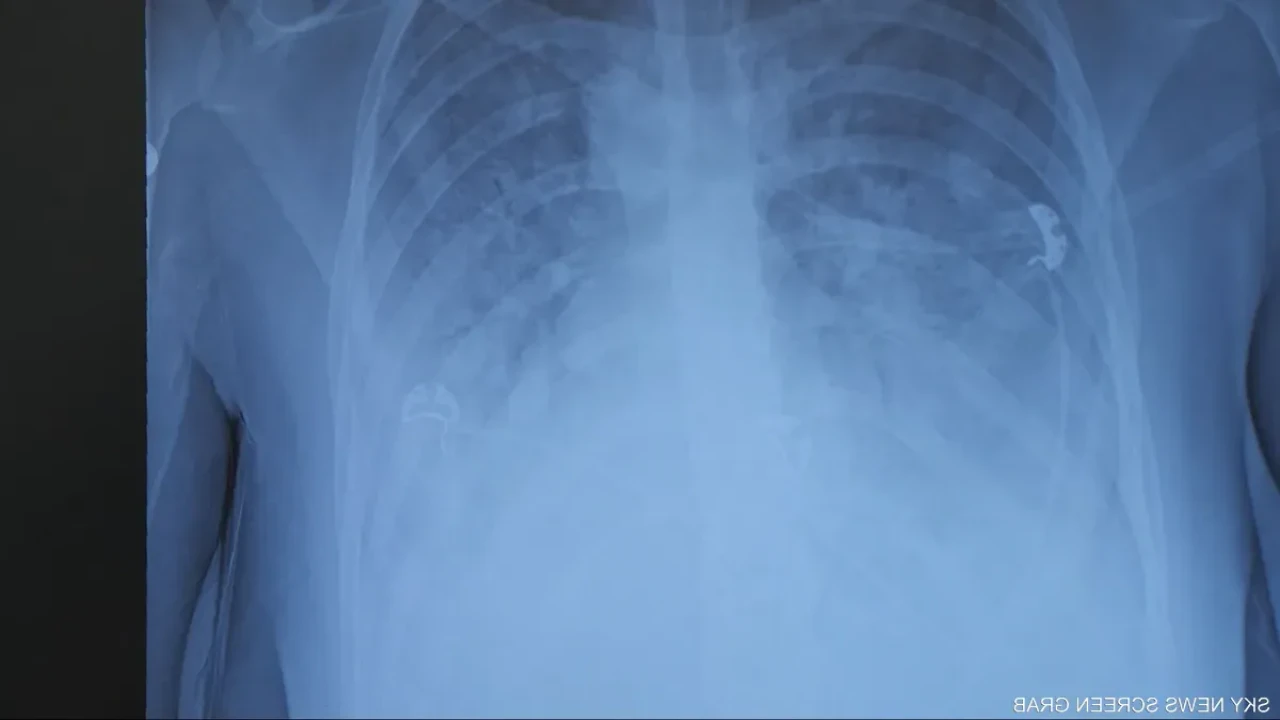

Ürdün’de 16 yaşındaki genç, bir yıl boyunca gizli gizli elektronik sigara kullandıktan sonra "patlamış mısır akciğeri"ne yakalandı. Artık ömür boyu oksijen bağımlısı.

Bir yıl boyunca gizlice elektronik sigara kullanan 16 yaşındaki Ürdünlü genç, kalıcı akciğer hasarına yol açan nadir bir hastalığa yakalandı. Genç artık hayatı boyunca oksijen tüpü taşımak zorunda.

Ürdün’de yaşanan trajik olay, elektronik sigaranın gençler üzerindeki etkilerine dair endişeleri bir kez daha gündeme taşıdı. 16 yaşındaki bir genç, yaklaşık bir yıl boyunca ailesinden gizli şekilde elektronik sigara (vape) kullandıktan sonra, tıbbi adı bronşiolitis obliterans olan ve halk arasında “patlamış mısır akciğeri” olarak bilinen ciddi bir solunum hastalığına yakalandı.

Solunum yetmezliği nedeniyle hastaneye kaldırılan genç, artık taşınabilir oksijen tüpü olmadan nefes alamıyor. Doktorlar, genç hastanın ömür boyu oksijen desteğine ihtiyaç duyacağını belirtiyor. Oksijen cihazıyla birlikte okuluna devam eden genç, yaşıtlarının aksine artık hiçbir fiziksel aktiviteye katılamıyor.